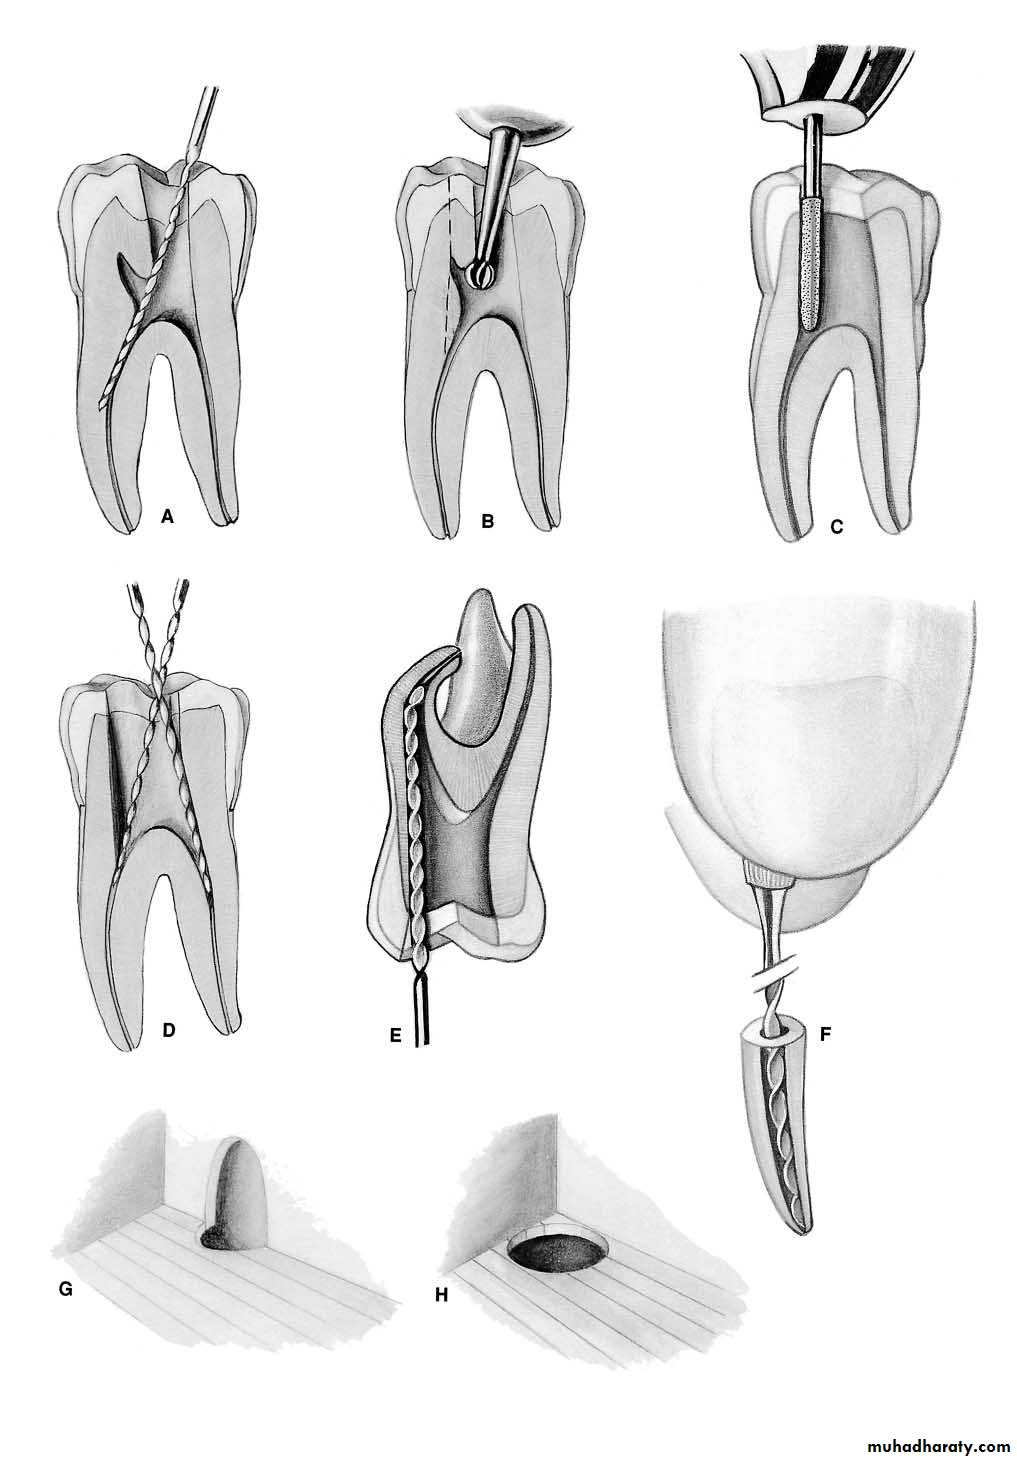

A curved canal is enlarged by alternate reaming and filing with copious irrigation

Maxillary Premolar TeethErrors in Cavity Preparation

A.UNDEREXTENDED: preparation exposing only pulp horns. Control of enlarging instruments is abdicated to cavity walls. The white color of the roof of the chamber is a clue to a shallow cavity. B.OVEREXTENDED: preparation from a fruitless search for a receded pulp. The enamel walls have been completely undermined. Gouging relates to failure to refer to the radiograph, which clearly indicates pulp recession.C.PERFORATION: at the mesiocervical indentation. Failure to observe the distal-axial inclination of the tooth led to bypassing receded pulp and perforation. The maxillary first premolar is one of the most commonly perforated teeth.

D.FAULTY ALIGNMENT: of the access cavity through full veneer restoration placed to “straighten” the crown of a rotated tooth. Careful examination of the radiograph would reveal the rotated body of the tooth.E.BROKEN INSTRUMENT: twisted off in a“cross-over” canal. This frequent occurrence may be obviated by extending the internal preparation to straighten the canals (dotted line).

F.FAILURE to explore: débride, and obturate the third canal of the maxillary first premolar (6% of the time). G.FAILURE to explore: débride, and obturate the second canal of the maxillary second premolar (24%of the time).

Mandibular Premolar TeethErrors in cavity Preparation

A.PERFORATION: at the distogingival caused by failure to recognize that the premolar has tilted to the distal.B.INCOMPLETE: preparation and possible instrument breakage caused by total loss of instrumentcontrol. Use only occlusal access, never buccal or proximal accessC.BIFURCATION of a canal completely missed, caused by failure to adequately explore the canal with a curved instrument.D.APICAL PERFORATION of an invitingly straight conical canal. Failure to establish the exact length of the tooth leads to trephination of the foramen.

E.PERFORATION: at the apical curvature caused by failure to recognize, by exploration, buccal curvature. A standard buccolingual radiograph will not show buccal or lingual curvature.